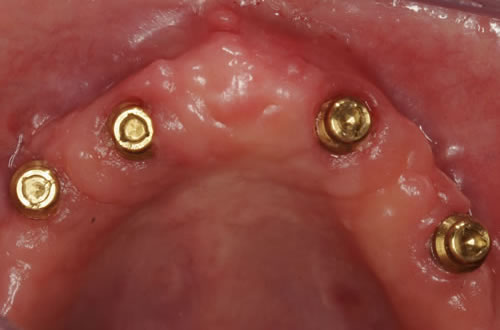

Abb. 3.7: Individuelle Stegversorgung aus Stahl auf vier Implantaten im zahnlosen Unterkiefer.

Abb. 3.8: Individuelle Stegversorgung aus Gold auf vier Implantaten im zahnlosen Unterkiefer.

Diese Beispiele ließen sich endlos fortführen. Sie zeigen die Probleme bei der Versorgung zahnloser Kiefer, wie sie immer wieder geschildert werden. Mit Hilfe sehr einfacher Maßnahmen kann durch die Einpflanzung künstlicher Zahnwurzeln eine instabile Prothese soweit befestigt werden, dass die Kau- und Sprechfunktion wieder hergestellt ist. Manchmal kann die alte Prothese weiterverwendet werden, in dem man in die Prothesenbasis Sekundärteile einarbeitet, die für Halt sorgen (Abb. 3.5, 3.6). Bei aufwendigeren Steg- oder Teleskoparbeiten muss auch der Zahnersatz der auf den Implantaten fixiert wird neu angefertigt werden. Diese Arbeiten werden dann brückenartig und sehr grazil gestaltet. (Abb. 3.7 bis 3.12).